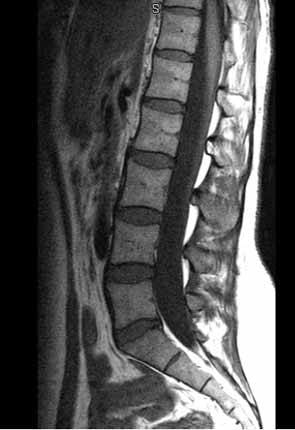

Spinal cord injuries usually begin with a blow that fractures or dislocates your vertebrae, the bone disks that make up your spine. Most injuries don't sever your spinal cord. Instead, they cause damage when pieces of vertebrae tear into cord tissue or press down on the nerve parts that carry signals. In a complete spinal cord injury, the cord can't relay messages below the level of the injury. As a result, you are paralyzed below the level of injury. In an incomplete injury, you have some movement and sensation below the injury.

Whether the cause is traumatic or nontraumatic, the damage affects the nerve fibers passing through the injured area and may impair part or all of your corresponding muscles and nerves below the injury site. Spinal injuries occur most frequently in the neck (cervical) and lower back (thoracic and lumbar) areas. A thoracic or lumbar injury can affect leg, bowel and bladder control, and sexual function. A cervical injury may affect breathing as well as movements of your upper and lower limbs.

The spinal cord ends at the lower border of the first vertebra in your lower back ¡ª known as a lumbar vertebra. So injuries below this vertebra actually don't involve the spinal cord. However, an injury to this part of your back or pelvis may damage nerve roots in the area and may cause some loss of function in the legs, as well as difficulty with bowel and bladder control and sexual function.

Acupuncture Treatment of Spinal Cord Injuries

The mechanism of acupuncture treatment of spinal cord injuries includes 1)stimulation of the peripheral nerve ending (receptors) so to enhance the communications between the effectors and central nervous system provided there is still connection, 2) improvement of circulation and elimination of blood congestion and qi stagnation, 3) facilitation of tissue healing around the injured spot, 4) induction of the repair of damaged nervous tissue.

Classical acupuncture treatment of spinal cord injuries consists of two parts: 1) systemic regulations by stimulating acupoints on the arms and legs which are the origins of the energy pathways--meridians, 2) spinal cord awaking process, that is to stimulate the 17 pairs of acupoints along the sides of the spinal column where the vertebral nerve roots emerge. Those 17 pairs of acupuncture are called Hua Tuo Spinal Points, named after the famous Chinese medicine doctor( 145-208). The acupoints are used to treat spinal cord injuries and internal conditions as well.